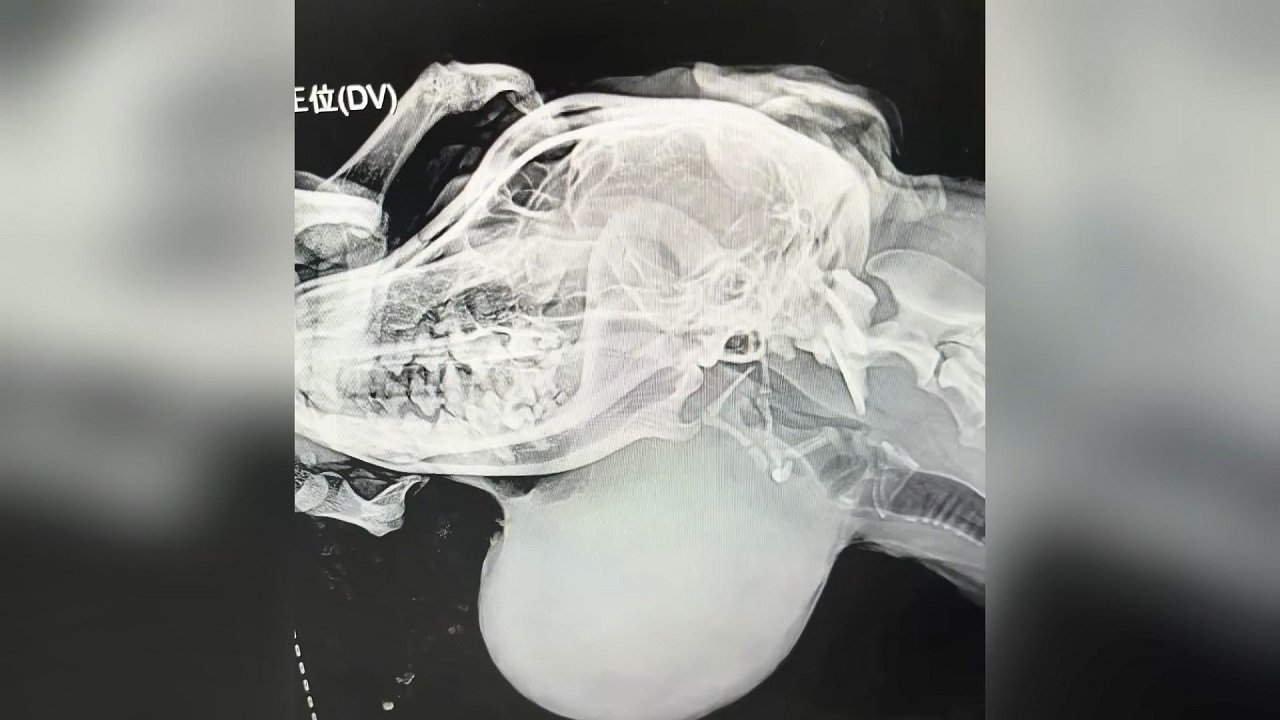

The X-ray confirmed it — the tumor was enormous. Whether it was malignant or benign was still unknown. Thankfully, his bloodwork came back normal. The vet suspected it was filled with lymphatic fluid and recommended draining it.